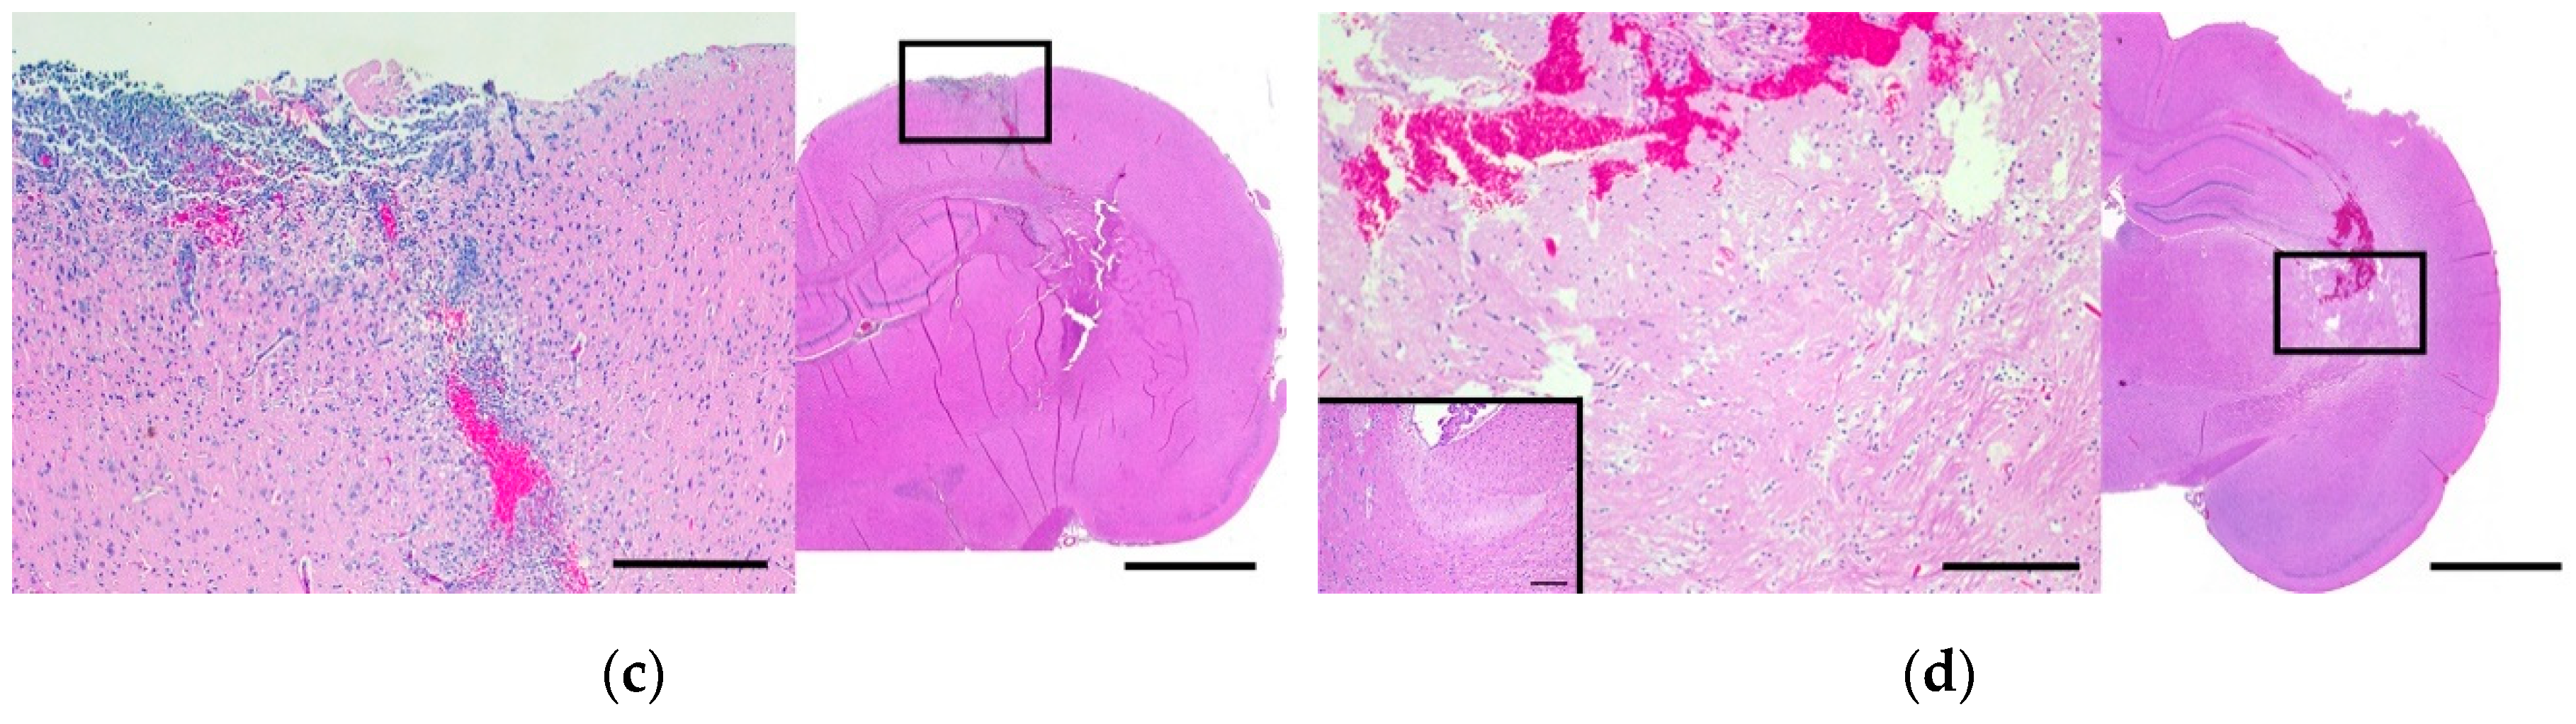

2.3. Histomorphologic Analyses

4.4. Histomorphologic Analyses of Gd-EBD Treated Rodents

| Category | Survival (h) | Grade 1 | Grade 2 | Grade 2a | Grade 2b | Grade 3a | Grade 4 |

|---|---|---|---|---|---|---|---|

| sham | sham, n = 2 | 2 | 0 | 0 | 0 | 0 | 0 |

| Immediate response | Burst100, n = 2 | 2 | 0 | 0 | 0 | 0 | 0 |

| 1, n = 2 | 2 | 0 | 0 | 0 | 0 | 0 | |

| 24, n = 4 | 4 | 0 | 0 | 0 | 0 | 0 | |

| 48, n = 4 | 4 | 0 | 0 | 0 | 0 | 0 | |

| Delayed response | 72, n = 4 | 1 | 1 | 2 | 0 | 0 | 0 |

| 96, n = 4 | 0 | 0 | 2 | 2 | 0 | 0 | |

| H-FIRE | H-FIRE, n = 2 | 0 | 0 | 0 | 0 | 1 | 1 |

| Score | Criteria: Brain Parenchyma Changes |

|---|---|

| 0 | No lesions apparent |

| 1 | Superficial cerebral contusion, edema, electrode tracks, +/- hemorrhage; lesions limited to electrode tracks |

| 2 | Superficial cerebral contusion, edema, electrode tracks, +/- hemorrhage, inflammation; lesions limited to electrode tracks |

| 3 | Parenchymal hemorrhagic necrosis/ablation localized to electrode tracks/tips |

| 4 | Regional parenchymal hemorrhagic necrosis/ablation (necrosis around and remote from needle tracks) |

| Criteria: Meningeal Changes * | |

| a | Mild meningeal inflammatory infiltrates; limited locally to electrode insertion areas |

| b | Moderate meningeal inflammatory infiltrates; meningeal involvement throughout surgical site |

| c | Severe meningeal inflammatory infiltrates; diffuse meningitis extending beyond surgical field |